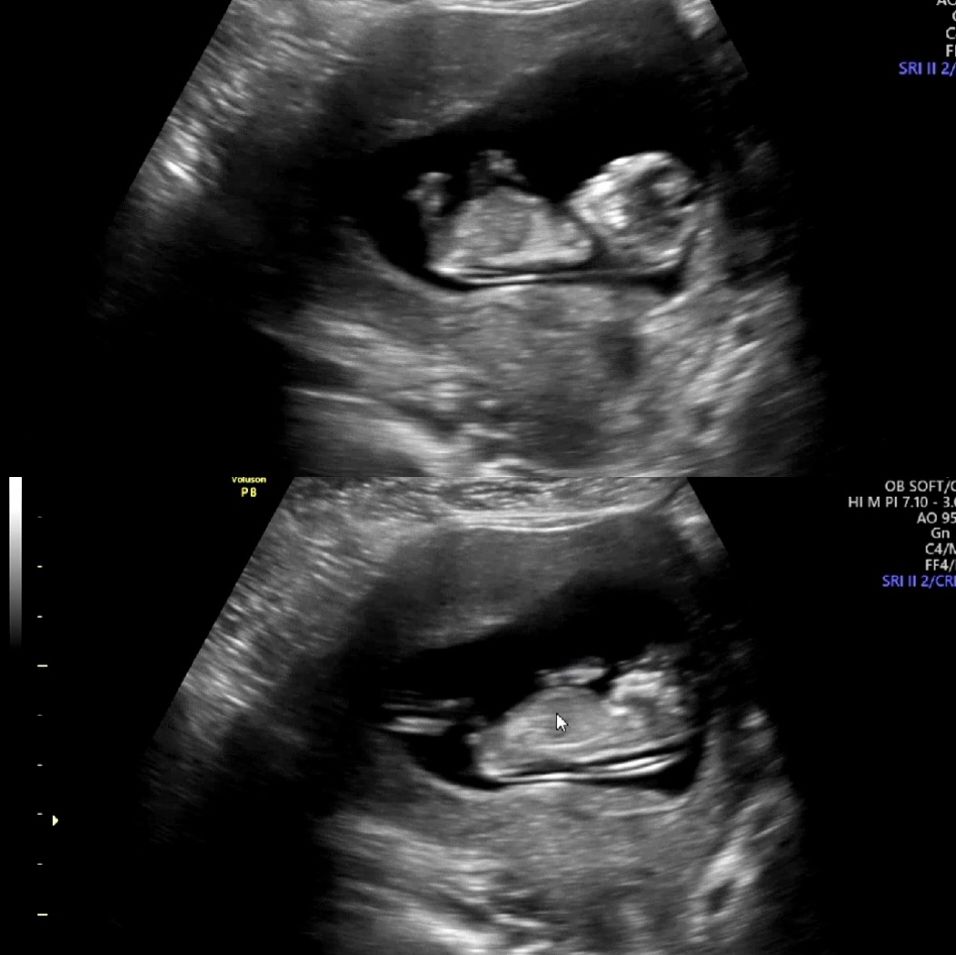

각도법 고수님계시나용

11주 4일 사진인데 ,, 사진보면 다리사이에 동그란게 🌶인가영..?ㅋㅋㅋㅋㅋㅋ